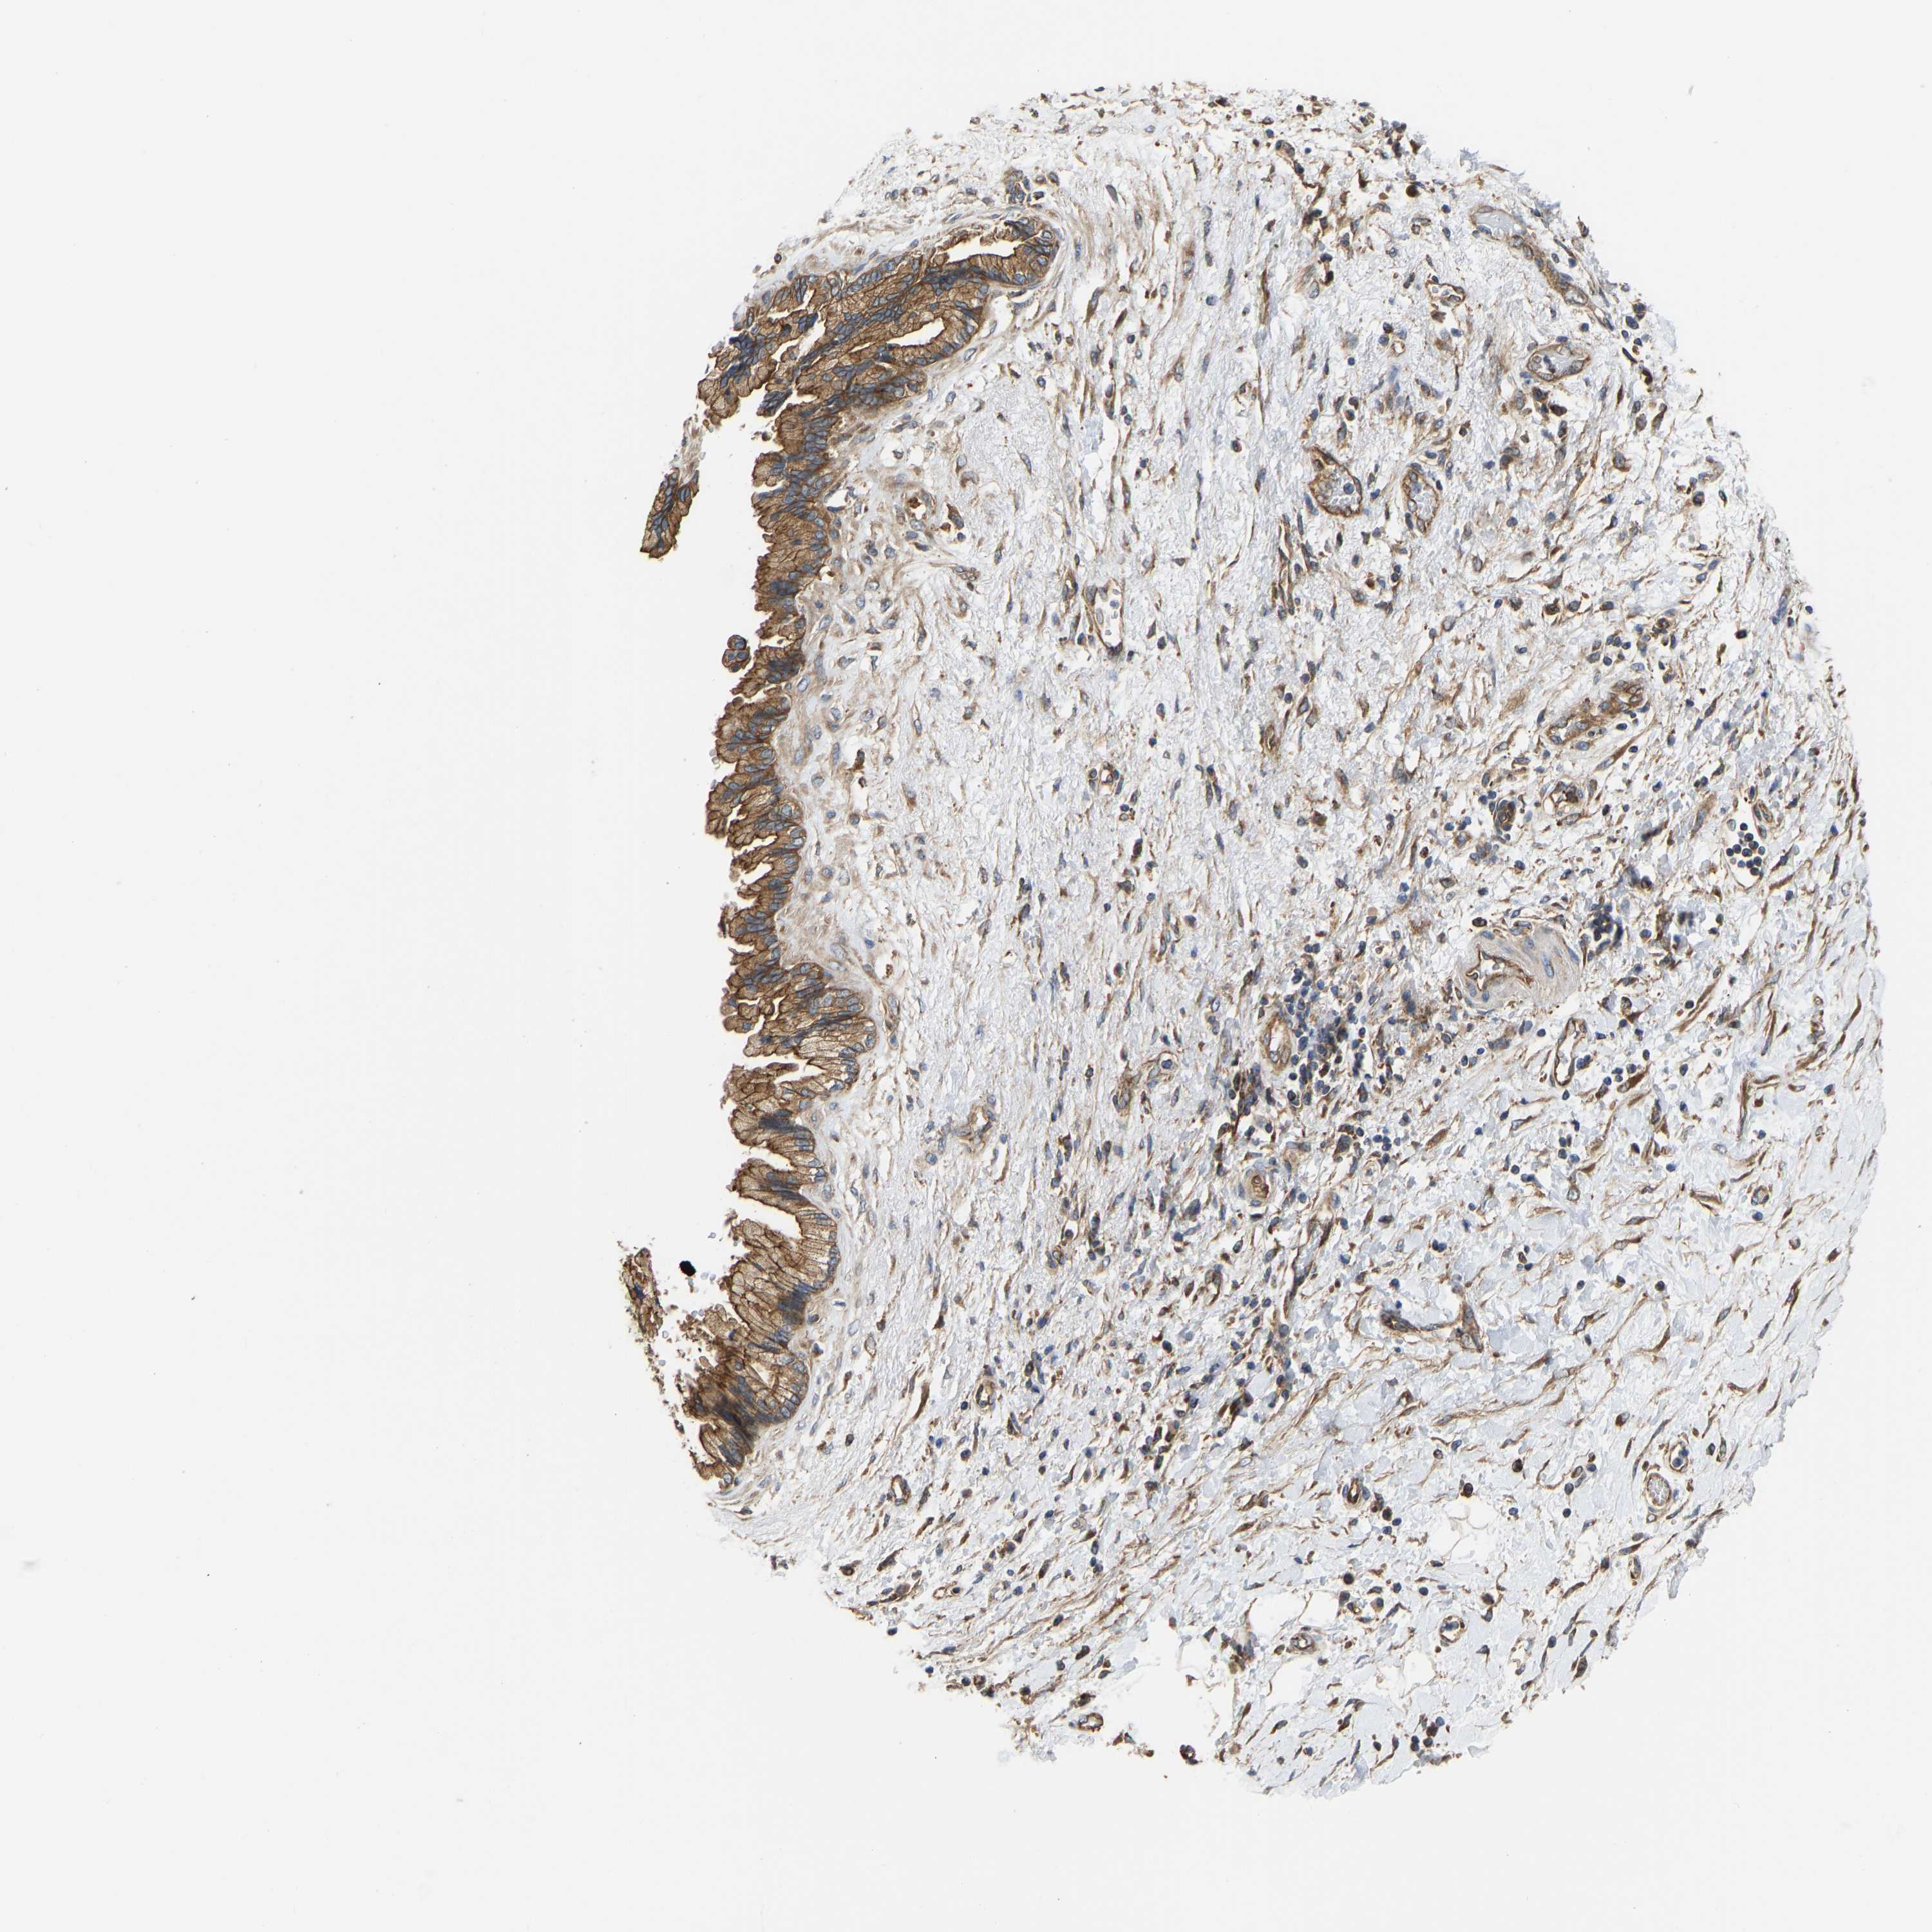

PANCREATIC CANCER - Protein expressioni

A mouse-over function shows sample information and annotation data. Click on an image to view it in a full screen mode. Samples can be filtered based on level of antibody staining by selecting one or several of the following categories: high, medium, low and not detected. The assay and annotation is described here.

Note that samples used for immunohistochemistry by the Human Protein Atlas do not correspond to samples in the TCGA dataset.

Antibody stainingi

Antibody staining in the annotated cell types in the current human tissue is reported as not detected, low, medium, or high, based on conventional immunohistochemistry profiling in selected tissues. This score is based on the combination of the staining intensity and fraction of stained cells.

Each image is clickable and will lead to virtual microscopy that enables deeper exploration of all samples and also displays staining intensity scores, fraction scores and subcellular localization as well as patient and tissue information for each sample.

Antibody HPA004747

Antibody CAB019322

High

Medium

Low

Not detected

Intensity

Strong

Moderate

Weak

Negative

Quantity

>75%

75%-25%

<25%

None

Location

Nuclear

Cytoplasmic/membranous

Cytoplasmic/membranous,nuclear

Adenocarcinoma, NOS